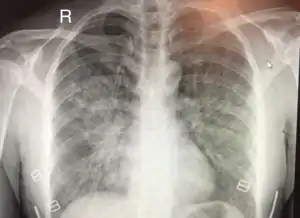

| Chest x-ray of HAPE showing characteristic patchy alveolar infiltrates with right middle lobe predominance. | |

Hypoxic pulmonary vasoconstriction (HPV) occurs diffusely, leading to arterial vasoconstriction in all areas of the lung. This is evidenced by the appearance of "diffuse," "fluffy," and "patchy" infiltrates described on imaging studies of climbers with known HAPE.[7]

On physical exam, increased breathing rates, increased heart rates, and a low-grade fever 38.5o (101.3o F) are common.[7][8] Listening to the lungs may reveal crackles in one or both lungs, often starting in the right middle lobe.[7][8] This can be seen on X-ray and CT imaging of the chest.[7][8] One distinct feature of HAPE is that pulse oximetry saturation levels (SpO2) are often decreased from what would be expected for the altitude. People typically do not appear as ill as SpO2 and chest X-ray films would suggest.[7][8] Giving extra oxygen rapidly improves symptoms and SpO2 values; in the setting of infiltrative changes on chest X-ray, this is nearly pathognomonic for HAPE.[8]